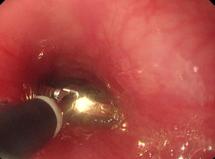

当日,妈妈带着月月来到彩虹医院呼吸二科门诊。呼吸二科副主任、主治医师张亚乐和医院重症医学科主治医师史斐娟根据患者描述,首先拍胸片后发现有纵膈移位,做CT查看。从CT显示的图像上发现,在小月月左侧下方支气管里有异物,管腔变窄。而月月妈妈贾女士回忆,孩子大年初一大人吃花生的时候,孩子有抓的动作,把花生壳咬碎了,当时在孩子嘴里也没有发现异物,所以就没有在意。当检查结果显示有异物,月月妈妈才想起来有这么回事。确定了气管里花生壳的位置后,张亚乐和史斐娟通过支气管镜,在月月全麻状态下,手术不到10分钟,用异物钳将这小半颗花生壳取了出来。术后月月的咳嗽、憋喘等症状顿时好转。

孩子家长感觉不妙,2月25日一大早,将孩子送到咸阳市彩虹医院就诊。经过CT检查,医生发现孩子主支气管有异物,是一整颗瓜子,必须尽快将异物取出。情况比较危急,医院呼吸二科副主任、主治医师张亚乐和医院重症医学科主治医师史斐娟当日下午就经过支气管镜将卡在主气管内的整颗西瓜子成功取出。